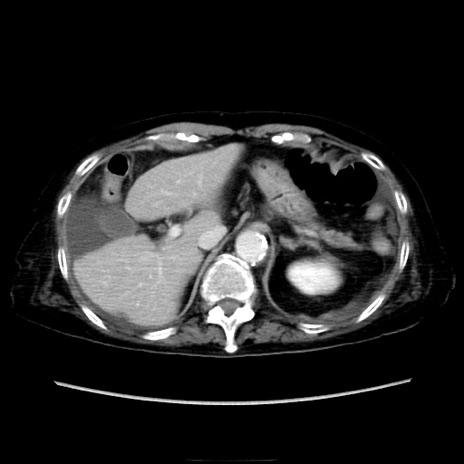

症例40(横断像)

【症例】90歳代女性

【主訴】腹痛・嘔吐

【現病歴】 食欲低下、嘔吐があり昨日他院受診。肺炎と診断され入院となる。入院後より腹部全体に圧痛あり。胃管留置され経過みていたが、症状持続するため、

当院転院となる。

【既往歴】胸椎圧迫骨折、胆石症

【身体所見】腹部:中央に激痛あり、圧痛あり、反跳痛不明

【データ】WBC 17100、CRP 18.82

横断像